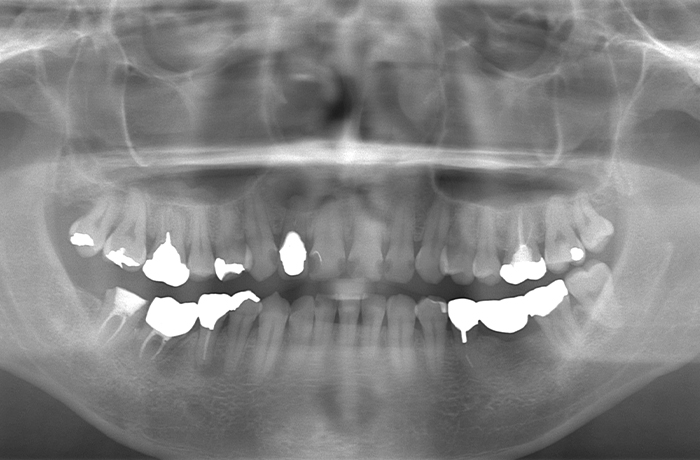

パノラマレントゲンおよびCT撮影により、右上2番(右上中央から2番目の前歯)は歯根周囲の骨吸収が進行し、保存困難歯と判断しました。

治療前

口腔内写真とレントゲン写真

右上2番は骨吸収が進み、動揺と咬合痛を伴っていました。

保存困難な状態であり、審美的にも歯頚ライン(歯の見えている部分と歯肉や顎骨に埋まっている部分の境界)の不調和が見られました。